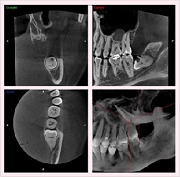

ですから、インプラントや歯周病などの診断に有効で、従来の平面画像では難しいとされた骨の幅の確認などが行えます。CT撮影で様々な角度から診断することで、正確な診査・診断に役立ち、より安全で確かな治療を行うことが可能となりました。

CT画像からは、骨の形や欠損状態がわかるだけでなく、神経の位置や向きなどもしっかり把握できますので、特に、以下のような治療で役立っています。

◆インプラント

◆歯周病治療

◆根管治療

◆親知らず